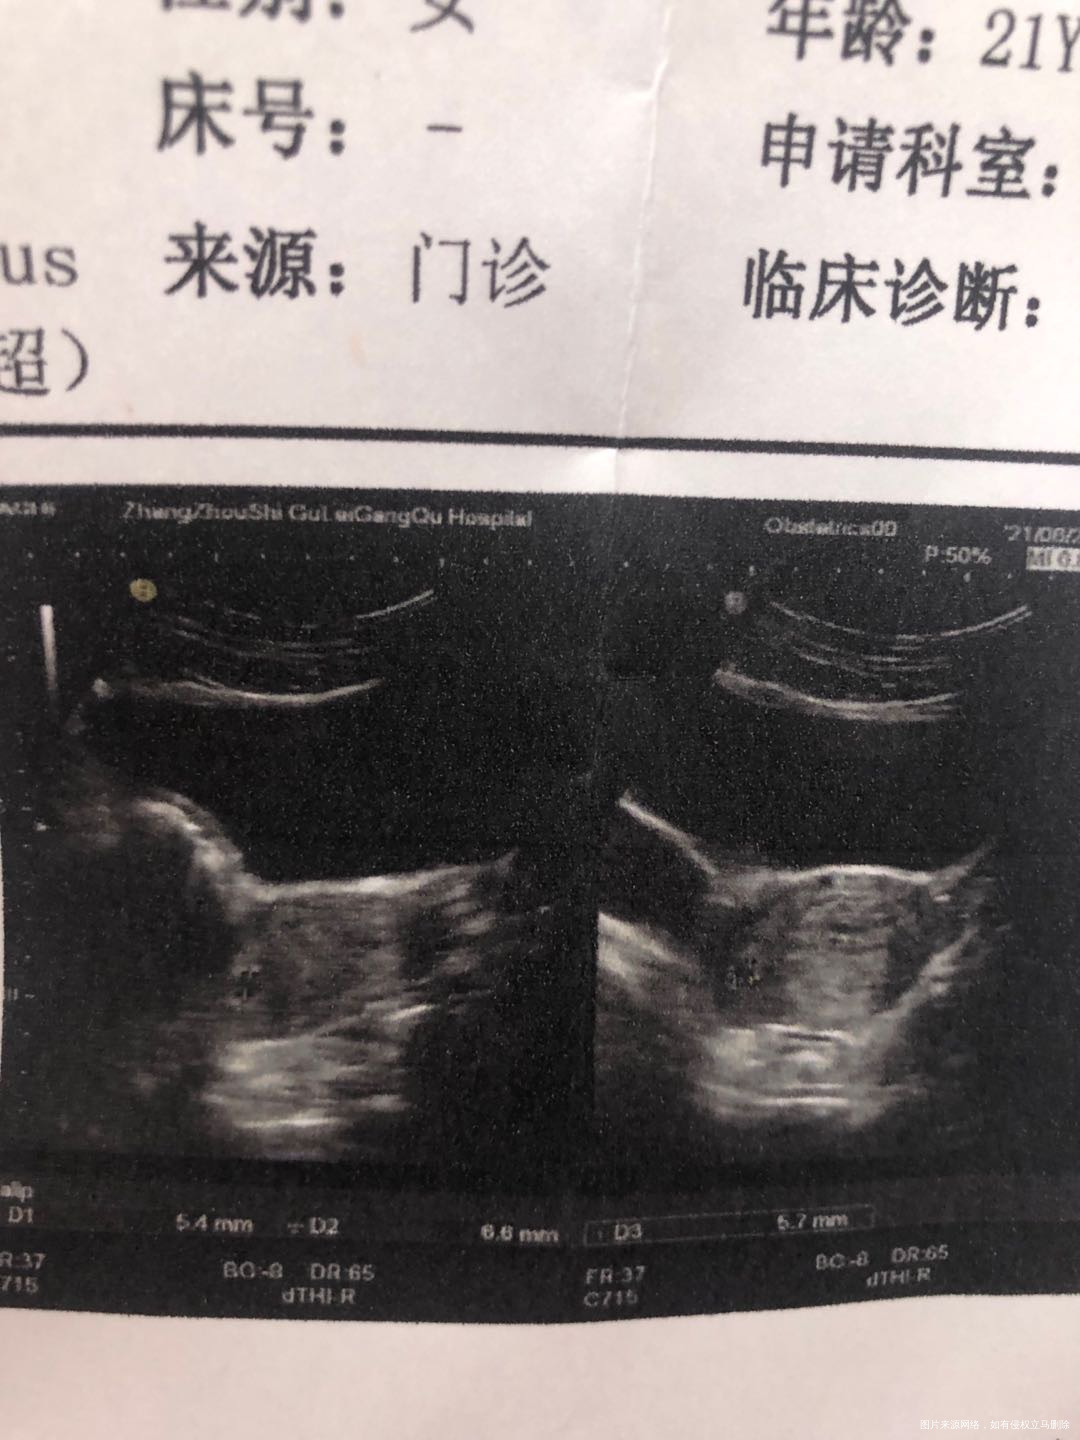

末次月经5月14日,第39天的时候做个b超,提示宫角孕,无腹痛,就一点粉色分泌物,上了两次小便擦了两次后就没有了,麻烦医生帮我看下是偏宫角还是宫角。

宫角妊娠 不是偏宫角 最好住院治疗

孕囊着床位置不会改变的

是的 本次妊娠风险大 最好尽快住院